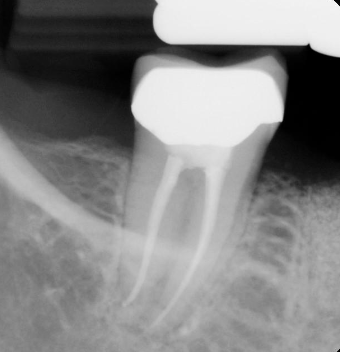

What are the steps for ridge preservation follow-up?

Take PA 3 mo after EXT to evaluate bone healing / degree of mineralization

Graft materials look “grainy” on PA

Dark areas indicate failing graft